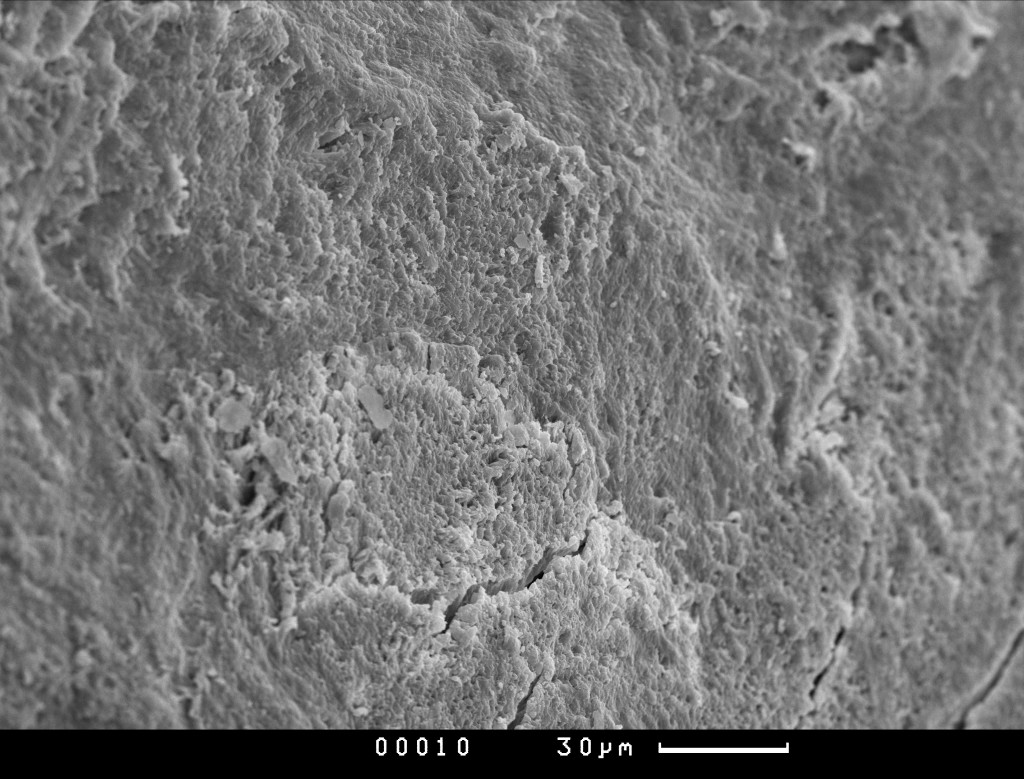

Материал БИОИМПЛАНТ ГАП - это 100% гидроксиаппатит в виде крошки или чипсов. Он представляет собой минеральный матрикс кости с сохраненной природной архитектоникой при полном отсутствии всех органических составляющих костной ткани. В отличие от синтетических материалов данный минеральный матрикс по химическому, морфологическому и структурному составу практически идентичен минеральному матриксу в кости человека. Выраженная топографическая шероховатость и хорошая пористость материала БИОИМПЛАНТ ГАП способствует более лучшей его фиксации и обеспечению размножения остеобластов, а также способствует миграции остеоцитов и ремодуляции костной ткани.

Чипсы Биоимплант ГАП после 1000гр Микросъемка производилась на СЭМ “CamScan S-4” фирмы Cambridge Instruments , Англия. Ускоряющее напряжение 20 кВ, режим регистрации вторичных электронов.

Чипсы Биоимплант ГАП после 1000гр Условия подготовки образцов и микросъемки в сканирующем электронном микроскопе (СЭМ)

Природная архитектоника материала БИОИМПЛАНТ ГАП представляет собой оптимальный каркас для прорастания кровеносных сосудов и глубокого проникновения клеток организма, участвующих в процессах остеосинтеза. Большая площадь поверхности и шероховатость материала БИОИМПЛАНТ ГАП обуславливает его высокую гидрофильность и, как следствие этого, приводит к быстрому впитыванию различных тканевых белков и крови , а также миграции в него клеток организма. Капиллярный эффект проникновения для любых жидкостей и клеток делает материал БИОИМПЛАНТ ГАП надежным и предсказуемым материалом в повседневной клинической практике.